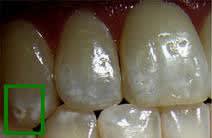

1/ MIH : Hypominéralisation Molaire-Incisive

PRÉVALENCE : 5 à 15%.

ASPECT CLINIQUE :

- Tâches opaques blanches/jaunes/brunes affectant les 1ères molaires permanentes (et dans 2 cas sur 3 les incisives de façon moins intense).

- Les contours sont nets, au contraire d'une fluorose dont les contours sont diffus.

- Les atteintes sont asymétriques, au contraire de presque tous les autres défauts d'émail : on peut voir une 16 très atteinte, une 26 indemne et une 36 modérément atteinte.

- Les autres dents sont indemnes.